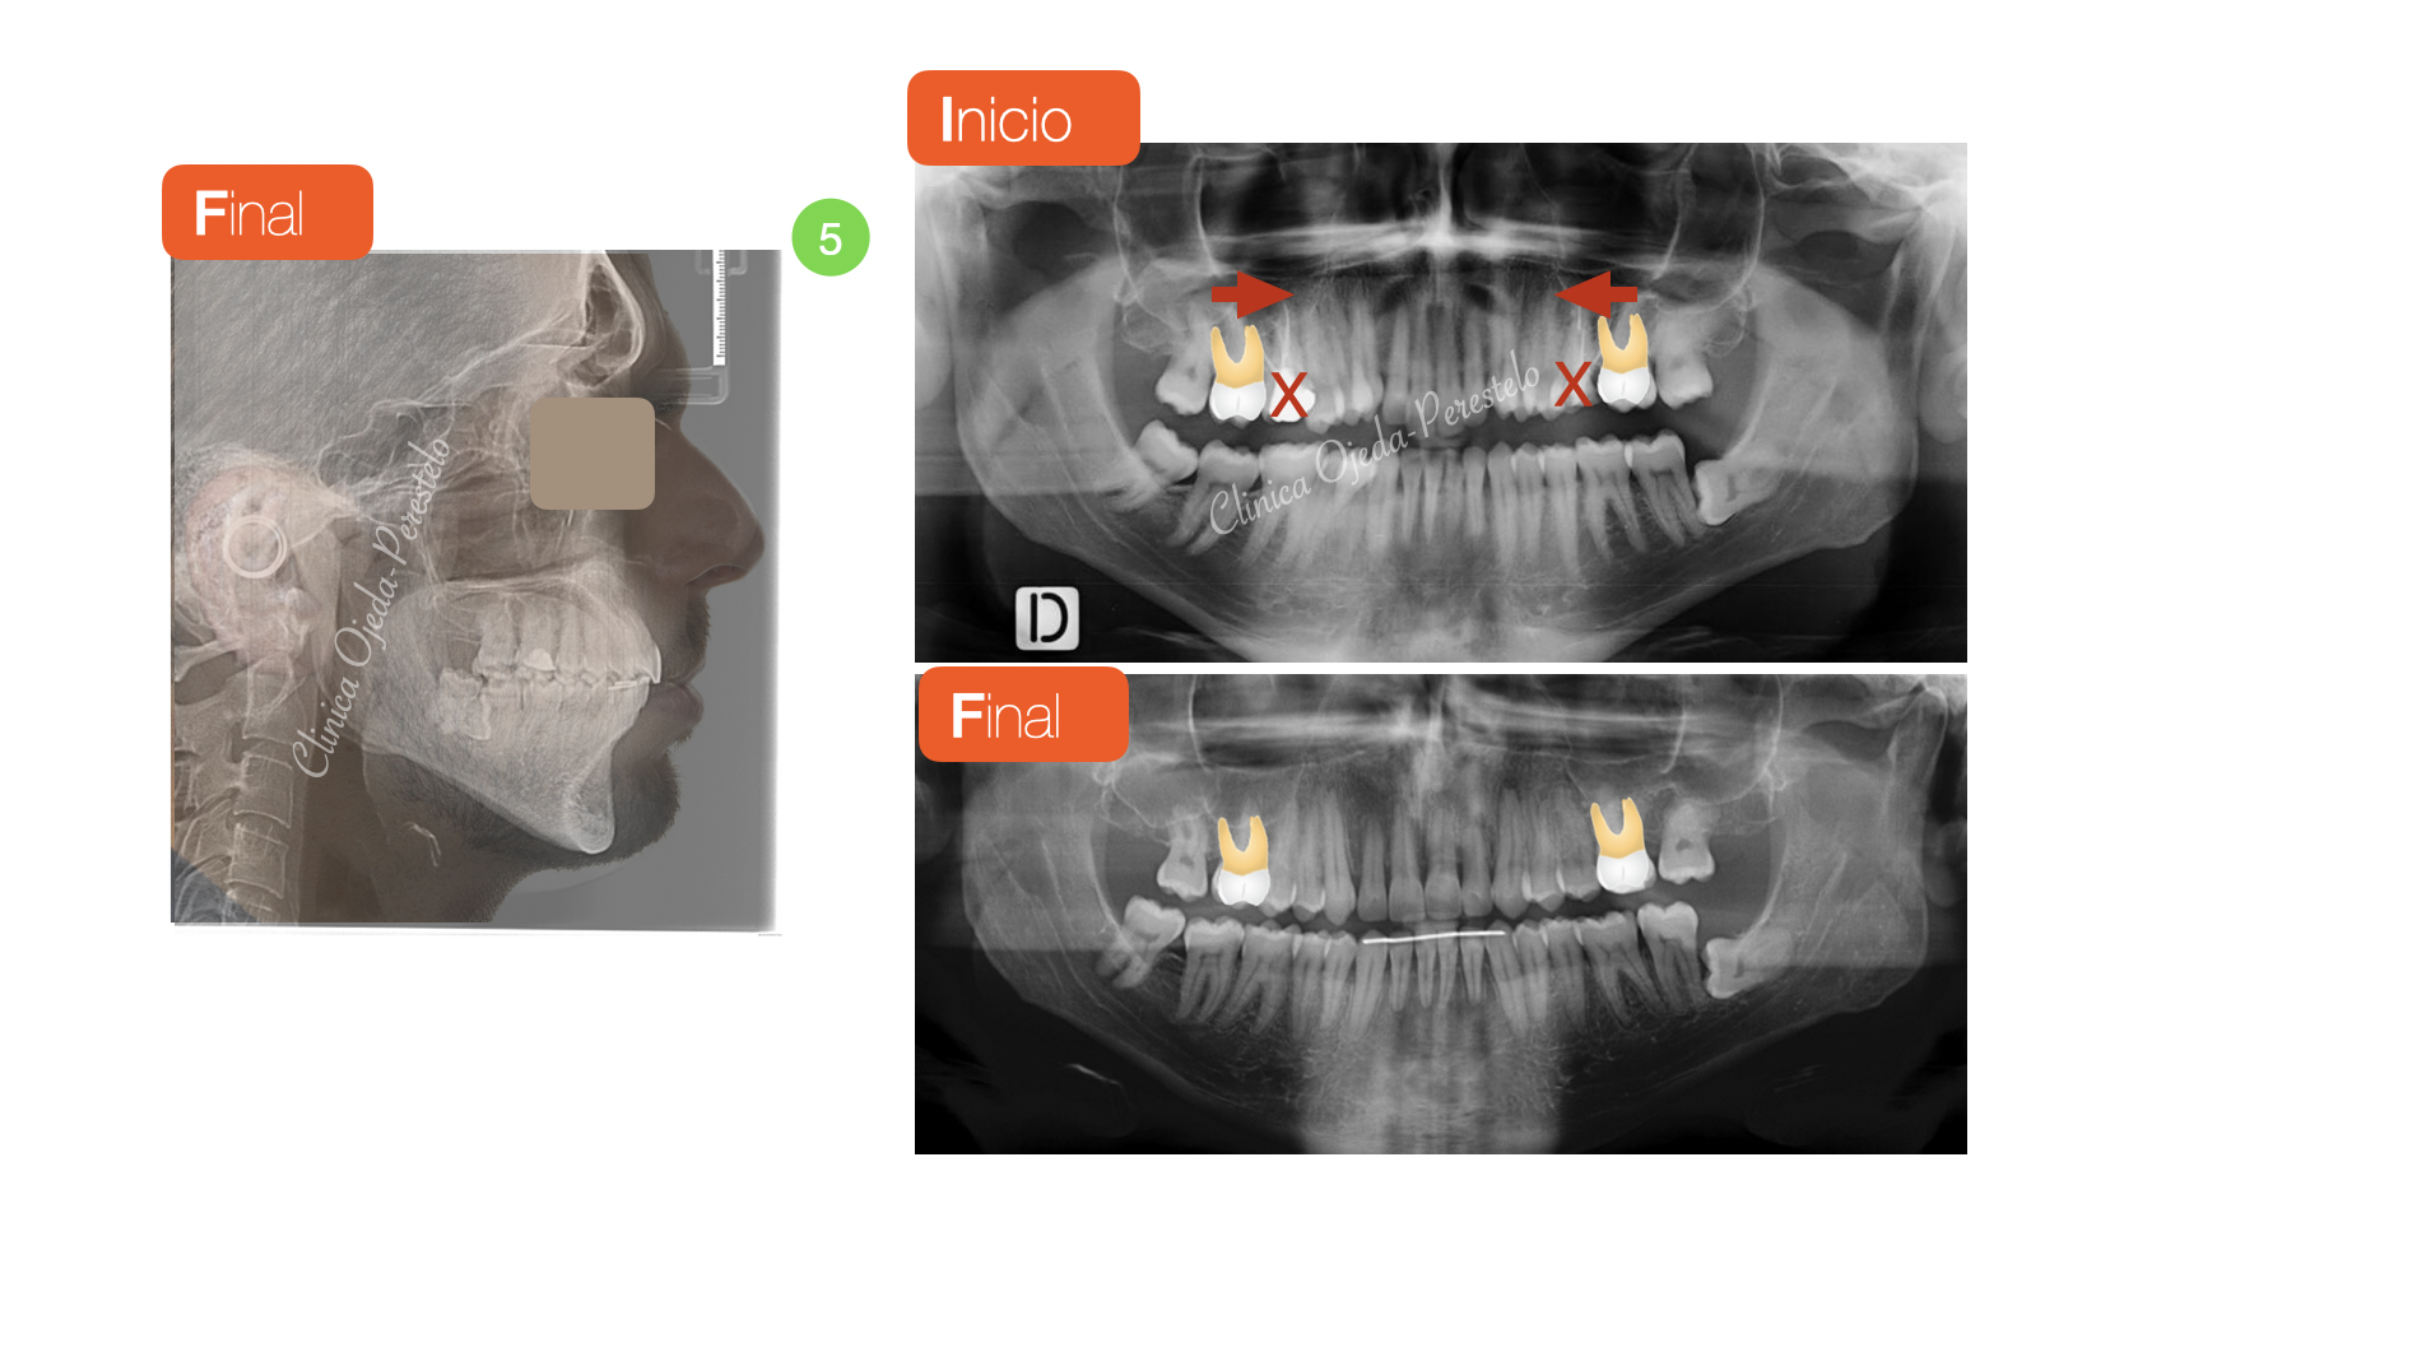

Apiñamiento severo con molares con mal pronóstico

Paciente tratado con brackets de autoligado pasivo (Sistema Damon) donde hemos alineado y nivelado desarrollando las arcadas. Este caso presenta la particularidad de haberse realizado las extracciones de los molares superiores (16,26 ) ya que los mismos  presentaban un mal pronóstico.

Quisieramos destacar cómo en la actualidad podemos realizar extracciones de molares en mal estado y cerrar dichos espacios SIN necesidad de colocar implantes o puentes y sin comprometer la estética ni la amplitud de la sonrisa.